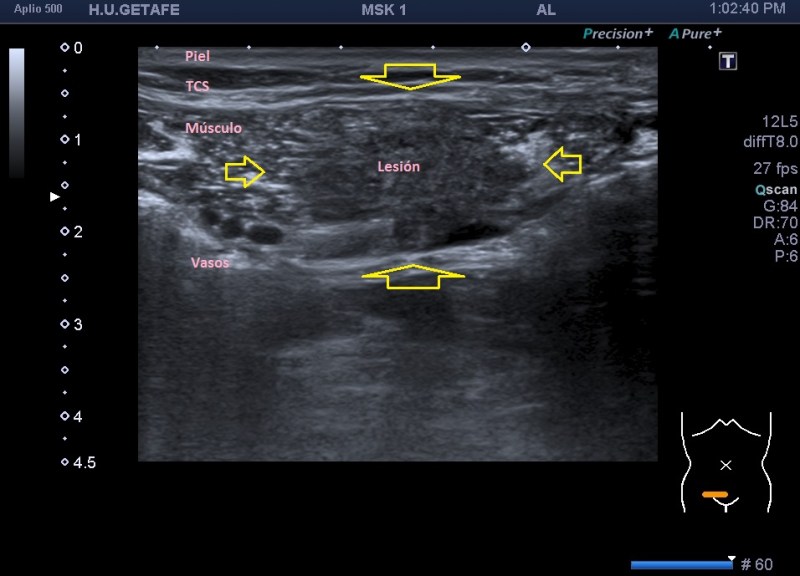

En cuanto la paciente me indicó su zona de dolor y pude el transductor observé una imagen mal definida que ocupaba la porción inferior del músculo recto abdominal derecho (coincidiendo con foco doloroso), se visualiza una lesión de ecogenicidad heterogénea (predominio hipoecogénico) con bordes irregulares de aproximadamente 2,5 cms en su eje más largo.

Semiológicamente es evidente una desestructura en el vientre muscular de recto anterior, que borra el aspecto normal del músculo y lo aumenta de tamaño aumentado su hipoecogenicidad. Los bordes son irregulares y de márgenes mal definidos.